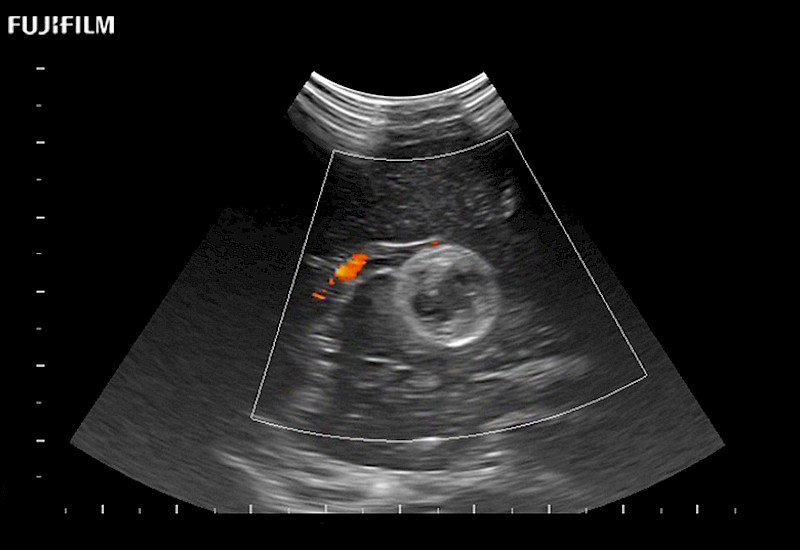

Smaller footprint (20mm) curved array transducer that is ideal for scanning during cranial guidance procedures.

Main Specifications: